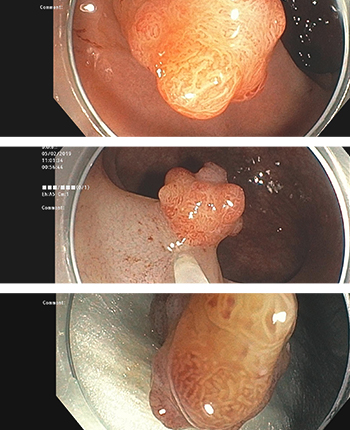

치료내시경 클리닉

위·대장 내시경 검사 중 당일치료 가능한 병변에 대해서는 신속한 시술 및 처치를 시행합니다.

7만사례 이상의 진단내시경과 3000사례 이상의 치료내시경을 시행한 내시경 전문의가 직접 시술 및 처치